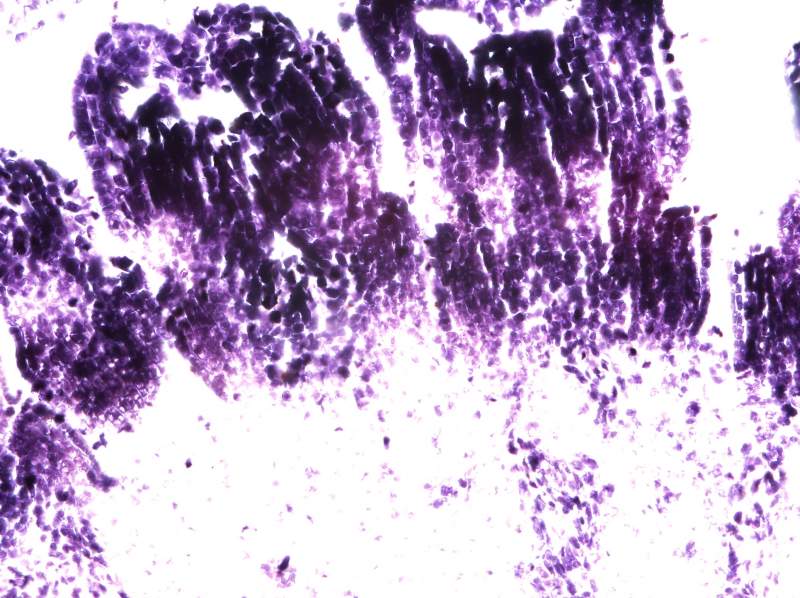

°¥£¬ËùÒÔºËÐļ¼Êõ»¹ÊÇÒª×Ô¼ºÕÆÎÕ²ÅÐÐ PSÓÖ²»ÊÇ×÷¼Ù£¬ÉúÎïѧ¿ÆÍ¼Æ¬µÄ´¦ÀíÓлù±¾µÄ¹æ¶¨£¬ÒªÊÇ˵È˼ÒÊÇPSµÄ£¬È˼ÒÁ˲»Æðµ÷Õûһ϶ԱȶÈÖ®À࣬¿Ï¶¨²»Äܰѿ´µÃ¼ûµÄµ÷ûÓУ¬Ã»¿´¼ûµÄµ÷³öÀ´£¬²»¶Ô½¹µ÷³É¶Ô½¹Êǰɣ¿£¡£¡£¡ÄãÈÃËûÈ¥µ÷£¬ÕâÖÖͼ¶¼¸Ð¾õ¶¼Ã»ÓжԽ¹£¬ÄãÈÃËûµ÷³öËûËùνµÄPSµÄЧ¹û£¬Ç°ÌåÊDz»Äܳ¬¹ýµ÷ÕûµÄ¹æ¶¨¡£²»È»µÄ»°Õâ¸öÕʼá¾ö²»´ò¸øËû¡£ |